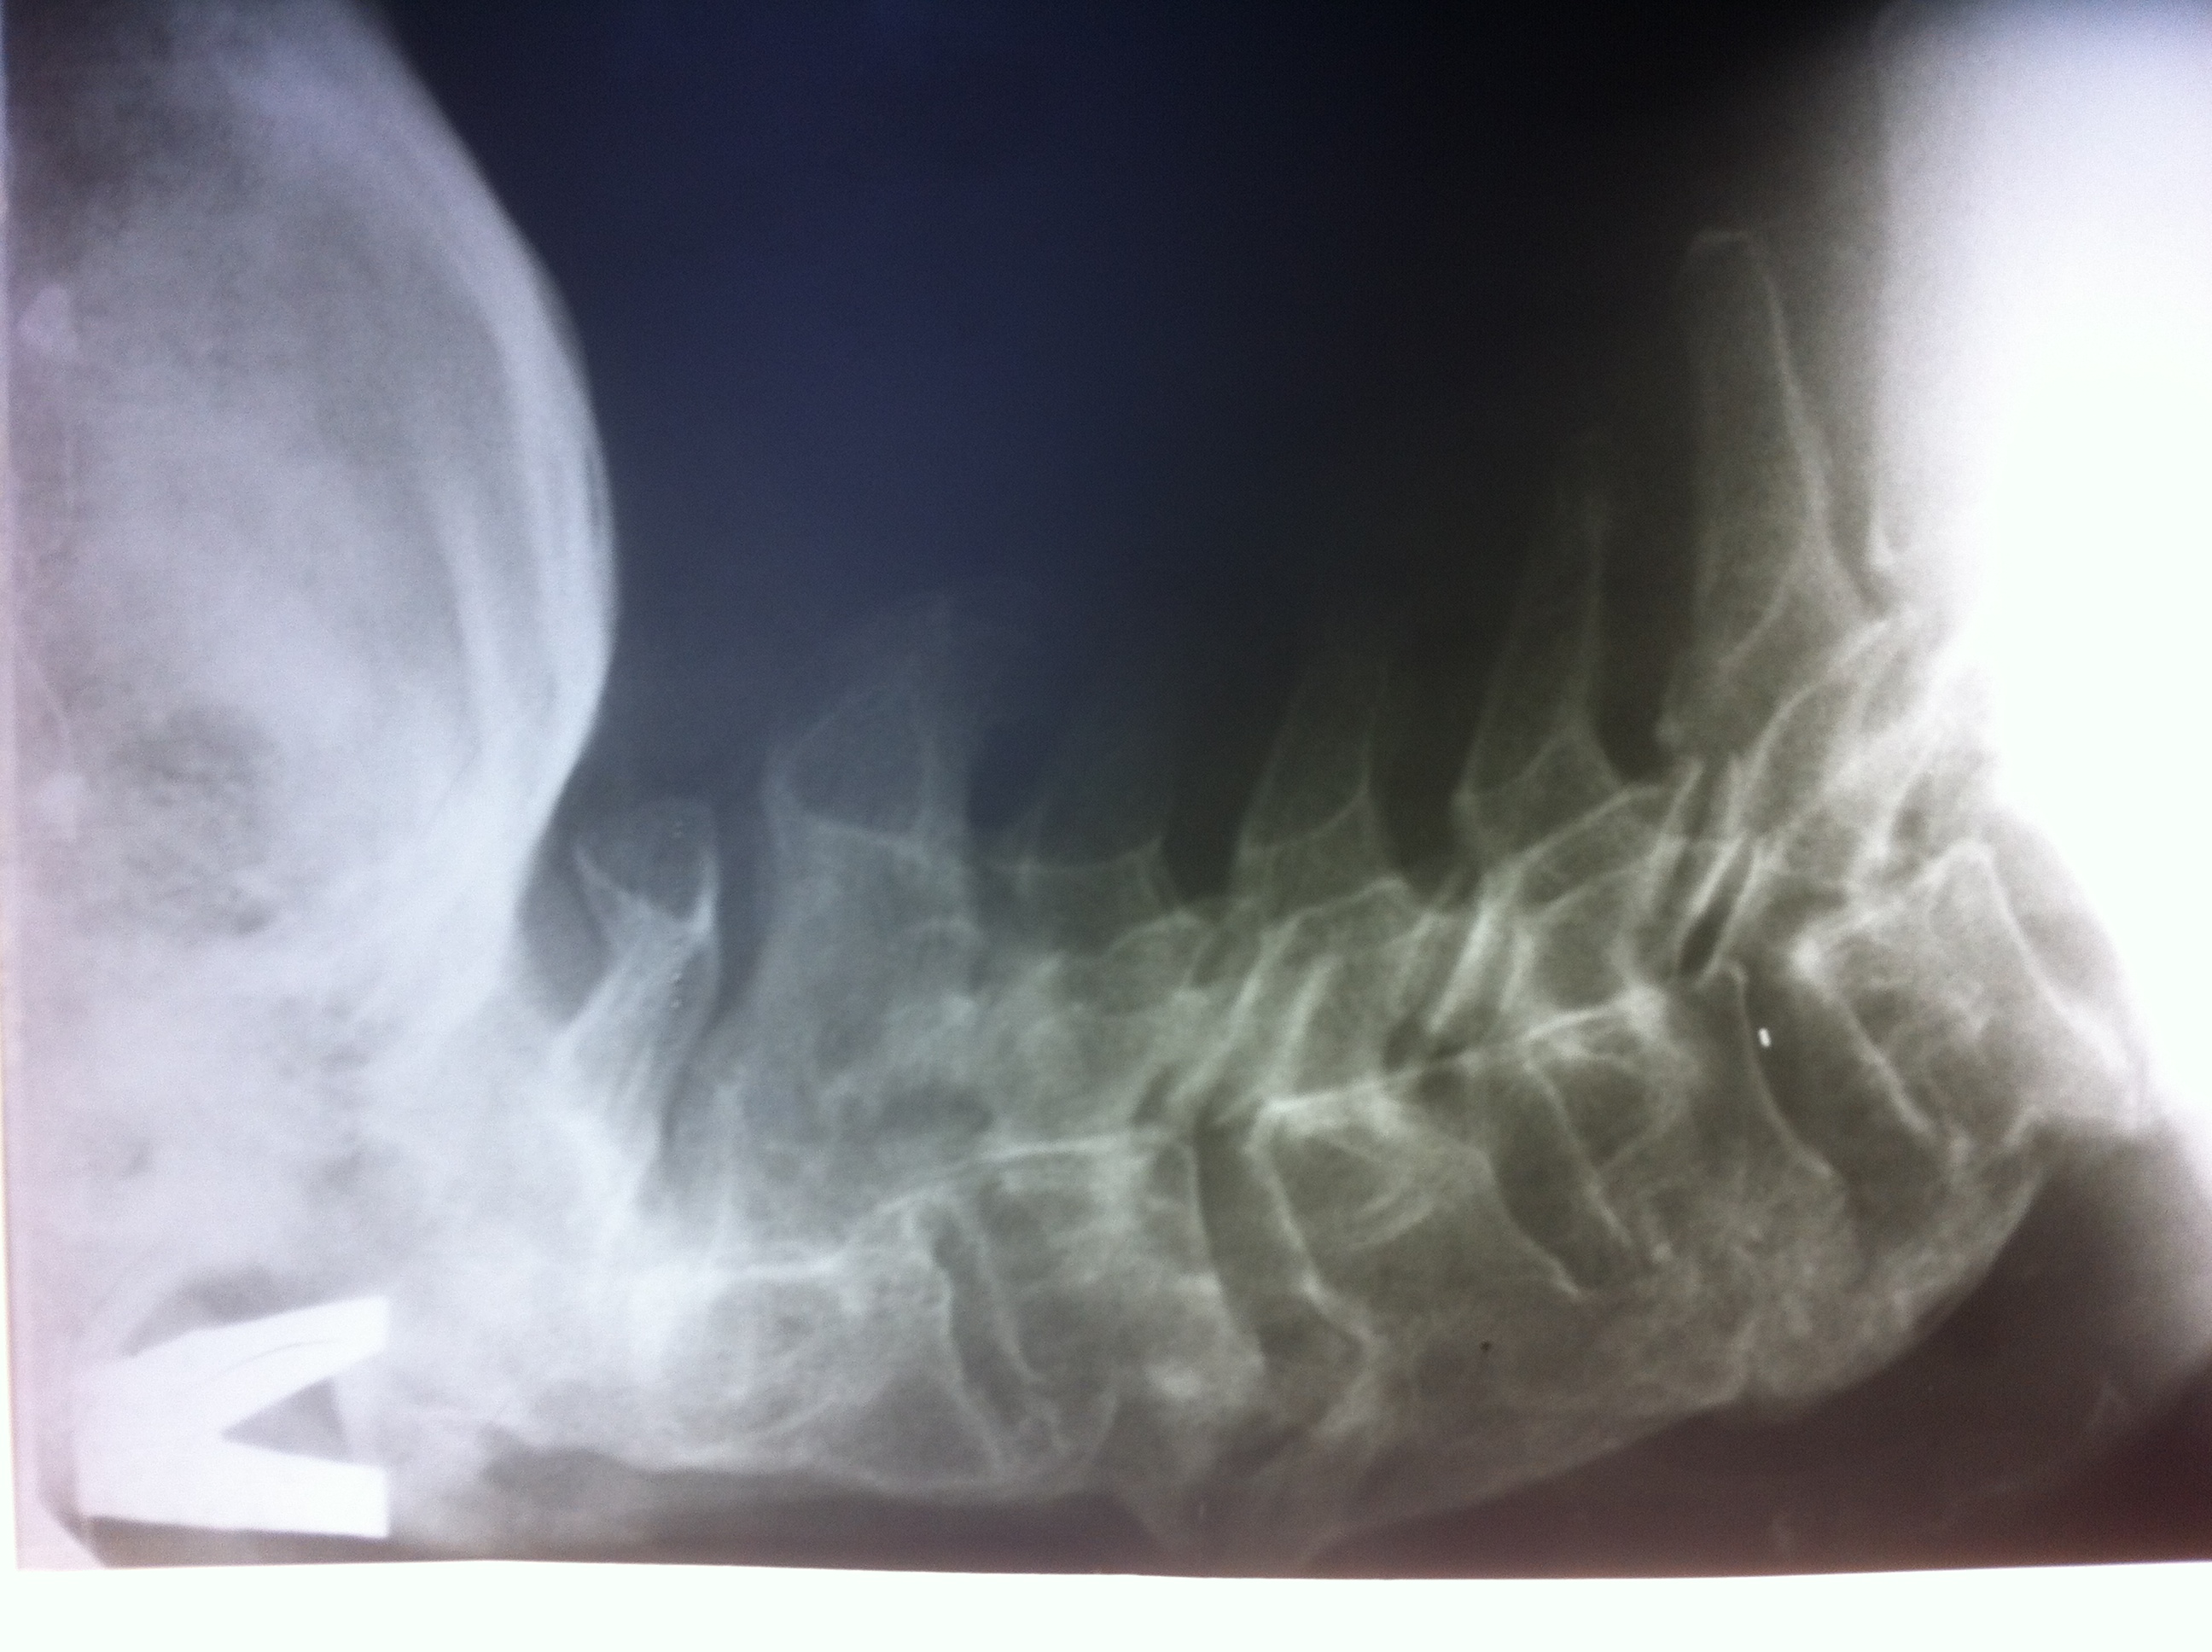

На рентгенограмме (рис. 1) и компьютерной томограмме шейного отдела позвоночника значимых признаков стеноза позвоночного канала нет; перелом тела позвонка С2 в стадии консолидации. Очевидных признаков объемных образований на уровне шеи нет. Грубые остеофиты по передней поверхности тел позвонков С3-С6, по размерам сопоставимые с размерами тел позвонков, с признаками грубой компрессии гортани и пищевода.

Рис. 1. Рентгенограмма шейного отдела позвоночника в боковой проекции